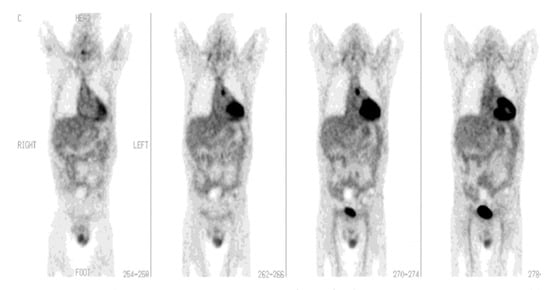

[18F]FDG-PET/CT has been found to play a role in the evaluation of endocarditis, myocarditis, and pericarditis. Transthoracic echocardiography along with blood culture has traditionally been a diagnostic modality of choice for detecting cardiovascular infections such as infective endocarditis (IE) [22]; IE poses a diagnostic dilemma due to its very diverse clinical presentation. The current method of diagnosis uses modified Duke criteria (MDC), which are divided into “major criteria” (typical blood culture and positive echocardiography) and “minor criteria” (predisposition, fever, vascular phenomena, immunologic phenomena, suggestive echocardiogram, and suggestive microbiologic findings). However, it creates a problem for patients with equivocal clinical symptoms in the absence of conventional echocardiographic features (particularly when prosthetic heart valves are present), making the diagnosis difficult [23]. Imaging modalities such as transesophageal echocardiogram (TEE), CT, and magnetic resonance imaging (MRI) have been studied. However, a number of technical factors, which include the presence of prosthetic heart valves and the aortic graft, prevent these imaging modalities from being accurate and reliable. PET/CT has demonstrated an advantage over echocardiography (Figure 3), especially in prosthetic valve endocarditis, but its role in native valve endocarditis is still unclear [24,25,26]. In such patients, when [18F]FDG-PET/CT is combined with MDC, the sensitivity of IE diagnosis appears to increase [27,28]. Additionally, there has also been an improvement in the diagnosis of symptomatic or asymptomatic septic embolism [28,29,30,31]. The detection of a septic embolism has also helped to change the therapeutic decision as its presence necessitates a longer duration of antibiotic treatment or timely surgical consultation. Furthermore, compared to PET/CT, PET/CT-angiography is able to detect considerably more abscesses and collections, as well as numerous lesions that are important for clinical and surgical decision-making [32]. However, leukocyte scintigraphy appears to be advantageous over [18F]FDG-PET/CT in the first 2 months post open cardiac surgery due to the possibility of a high and comparable level of radiotracer uptake in the inflammatory tissues [33].

Figure 3. PET/CT in infective endocarditis. The PET/CT image of a 47-year-old female with IE: (Upper) transaxial image; (lower) coronal image, with PET on the left and the PET/CT fusion image on the right. The images depict a focal region of increased [18F]FDG uptake in the heart at the position of the valvula aorta (with permission from reference [34]).